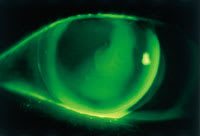

Our fitting objective was to select a diagnostic lens with a base curve that would be steep enough to clear the apex of the cornea and land on the flatter temporal mid-peripheral cornea from 1 o'clock to 6 o'clock (Figure 4). Ultimately, the patient was fit with a lens of 46.00 diopters, 3.25D, 10.4mm, visual acuity 20/25, with a comfortable wearing schedule of 14 to 16 hours a day.

Figure 4. Fluorescein pattern of with mid-peripheral bearing along the temporal (right side).